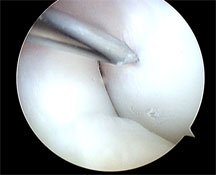

I decided to undertake microdrilling arthroscopically, which you can see in the second arthroscopic photo on the left of the needle being passed through a sheath and drilling into the underlying affected bone in order to release marrow cells and hopefully improve blood supply. I also inject PRP (platelet rich plasma) into the area.